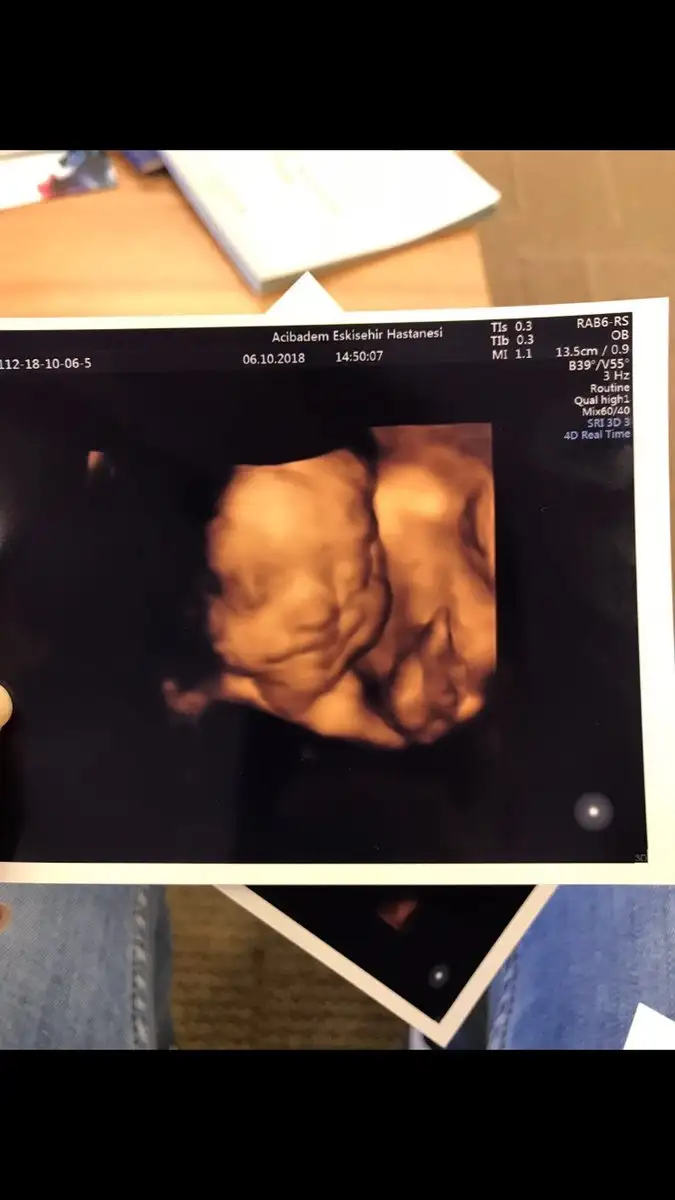

Oyyy minikkyaa bızım renklı pozlarımza bakın bugune dek bunları aldık 13haftalık biri dha 7cm orda

Bana da doktorum her gidişimde renkli görüntü verdi canım. Her defasında büyüdüğünü görmek çok güzel :)gecen bır arkadasıma da soyledım ankarada O. Ve gayet pahalı bır hastane. kadın renkli göstermemıs 17.haftada bıde dedım neden ses cıkarmıyorsun. ha şu da var benım hastaneme eşimın kuzenı gıdıyor o da daha alamamıstı onun dr.u baskası. nezaman verıyor dıye sordu bana benımkı verıyor dedım 13.haftadan buyana. dr.dan dr.a degısıyor demekkı canım![]()

evetttt yaaa resmen parmak kadarkenki halinden bebişliğe kadar olan sürecj göruyoruz nekadar şanslı bir donemdeyız kımbılır bızden sonra daha ne gelısmeler olacak şu teknolojide yerler onu pozlar hep aynı gb rahat glb ıcerde meleğinBana da doktorum her gidişimde renkli görüntü verdi canım. Her defasında büyüdüğünü görmek çok güzel :)